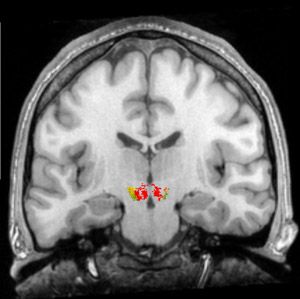

Zwei funktionelle Magnetresonanz-Tomografie-Aufnahmen vom VTA, © Kimberlee D'Ardenne, Science, 2008

Aktive VTA Dopamin-Nervenzellen von hinten

Lage des linken und rechten Mandelkerns Die Amygdala (Mandelkerne)1,9,10,11): Die Mandelkerne sind an allen angenehmen und unangenehmen Gefühlen als eine Art „Speicher-Verteiler-Zentrale“ beteiligt, nicht nur – wie sich mittlerweile auch in der deutschen Psychologen- und Psychotherapeuten-Szene herumgesprochen hat – an allen fünf Angststörungen und der Depression.

•   Das beidseitig am Boden des Mittelhirns (anat.: ventral) verlaufende Striatum (Streifengebilde), insbesondere sein Nucleus accumbens (Nacc)2,3,8,10), der zusammen mit dem Dopamin- und µ-Opioid-System unsere Lust-, Belohnungs- und Glücks-Leit- und Steuerzentrale ist.

(Bild unten): Vier fMRT-Scanner-Aufnahmen (coronal Aufnahmen, Durchsicht von vorne), während wir finanzielle Belohnungen (oder Bestrafungen) erwarten. Nur in der ersten Scanner-Aufnahme, links oben (a), während wir in freudiger Vorwegnahme, Erwartung und Vorfreude größer werdende Belohnungen (größere Geldgewinne, mehr Geld) erwarten, ist der Nacc aktiver3,10).

Die drei dimensionalen Ebenen des Gehirns 4 fMRT-Scanner-Aufnahmen vom Nucleus accumbens während der Erwartung größer werdender finanzieller Belohnungen und Bestrafungen

© 2001 by Knutson, NIH/NIAAA / USA